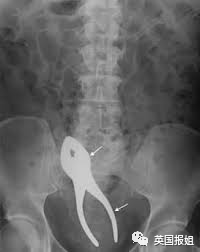

医生说,你永远无法想象病人的屁股里会卡进去些什么奇奇怪怪的东西,从日用百货到水果熟食一应俱全,被网友戏称为“菊花超市”。

医生表示,由于卡住的东西的形状、质感完全不同,医生们每次帮助病人做“菊花取物”的处理都特别麻烦。

甚至还发明出了灯泡卡臀时,接上灯座取出来的神技。

左:茄子 右上:铝罐 右下:咖啡罐

可以看出这些患者对于球形的、柱状的和长条形的物体有一些奇怪的执念。但有些患者也会突破这些形状的桎梏,寻找更多样的物品嵌入体内。

比如人人都知道放进去就取不出来的灯泡: